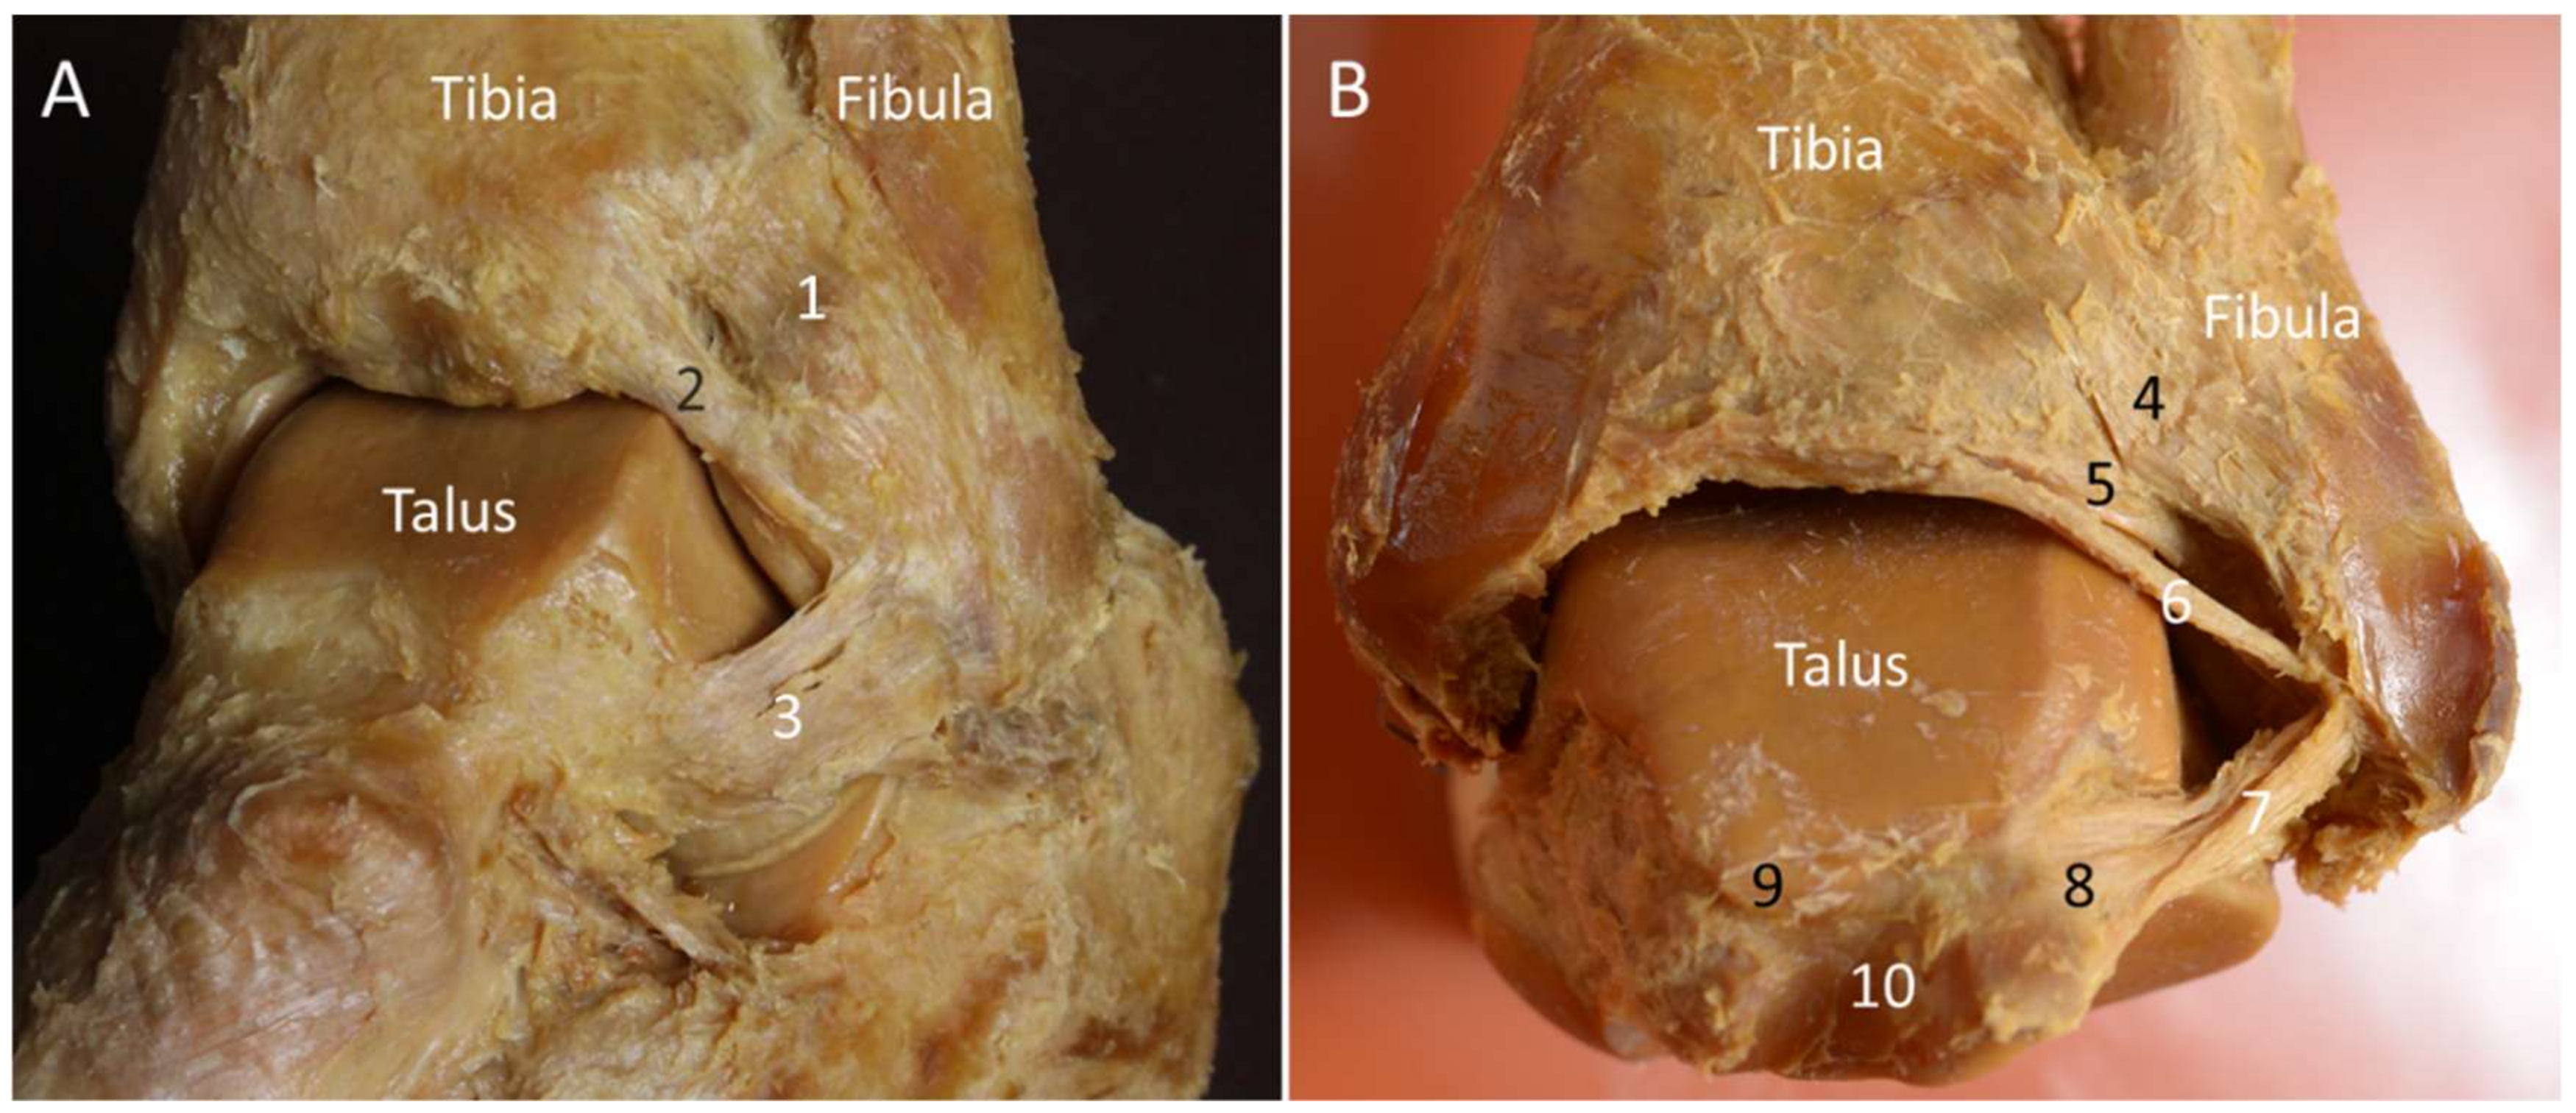

2.2. Posterior Inferior Tibiofibular Ligament

2.2.1. Anatomy

2.2.2. Scanning Technique

2.2.3. Clinical Relevance

2.3. Intermalleolar Ligament

2.3.1. Anatomy

2.3.2. Scanning Technique

2.3.3. Clinical Relevance